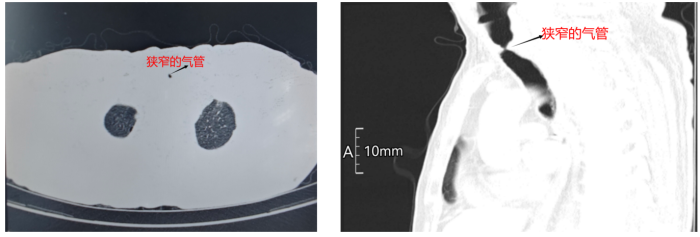

近日,一场与时间赛跑的抢救在遵义市第一人民医院紧张上演。一名气管最窄处仅3.5毫米、濒临窒息的患者,在呼吸与危重症医学科牵头、多学科团队的紧密协作下,通过高难度急诊介入手术成功打通堵塞的气道,最终转危为安。

55岁的王先生因“活动后气短半月,加重2天”被紧急送入遵义市第一人民医院呼吸重症监护室(RICU)。急诊胸部CT结果显示:气道出现严重狭窄,最窄处仅为3.5毫米,气管几乎完全堵塞。此时患者已呼吸急促、神志不清,血气分析提示存在“呼吸性酸中毒和急性Ⅱ型呼吸衰竭”,生命悬于一线。